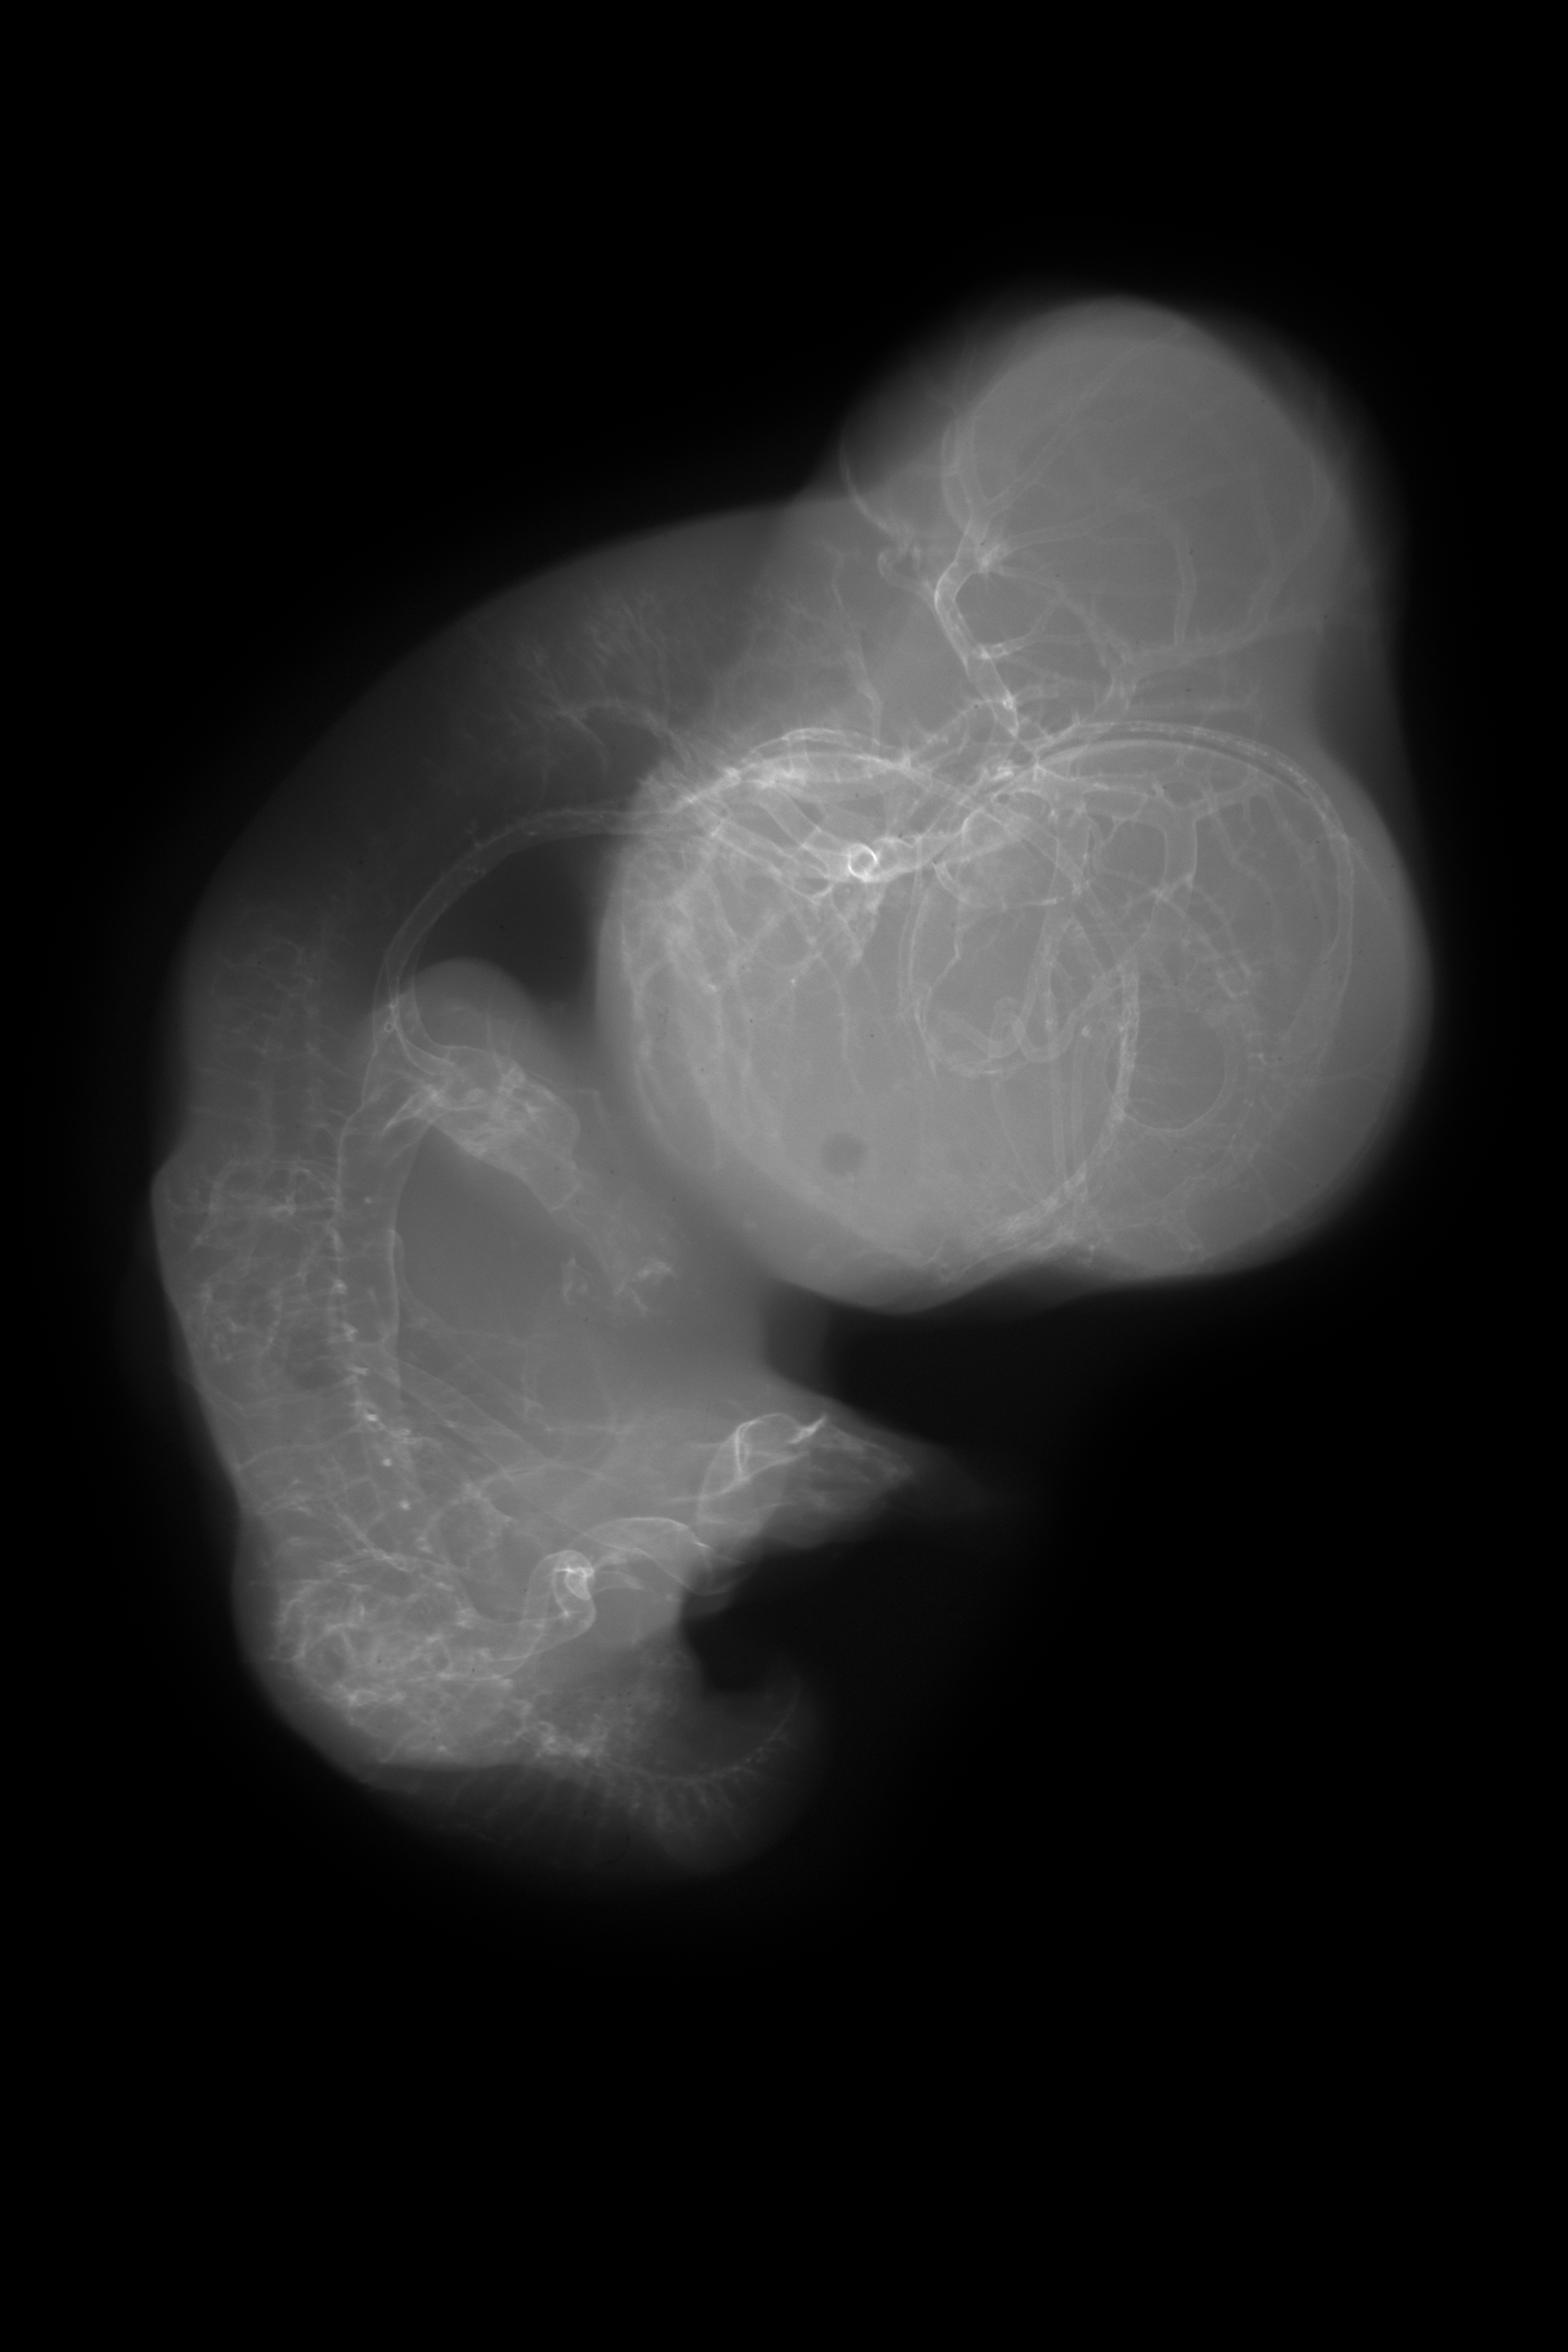

Chick Embryo Microangiography

Hamburger-Hamilton (HH) Stage 30 (approx. 6.5 days)

Stereo X-Ray Micrographs